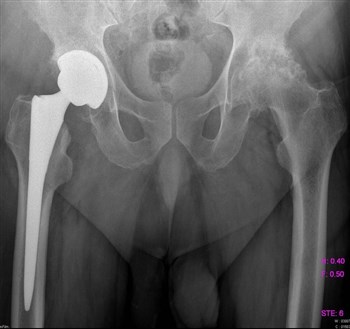

Артроз тазобедренного сустава

Все чаще и чаще пациенты обращаются с жалобами на боли в паху, в колене, иногда на боль в ноге, на скованность движений, нарушение походки.

Как правило, страдают таким недугом женщины после 40 лет.

Боль локализуется в вышеуказанных местах как на одной, так и на обеих ногах.

Для того, чтобы поставить верный диагноз, проводят диагностику, которая включает:

- МРТ;

- Рентгенографию;

- Компьютерную томографию.

Проведенная диагностика покажет, в какой стадии находится заболевание, будет дана точная информация о состоянии мягких и костных тканей.

Если заболевание не в хронической форме, или, проще говоря, не запущено, то лечение происходит обычным парацетамолом, без какого-либо хирургического вмешательства. Лечащий доктор назначает курс массажа, лечебной гимнастики, постоянный контроль ортопеда. При ноющих болях прописывается курс болеутоляющих – Кеторол, Диклофенак.